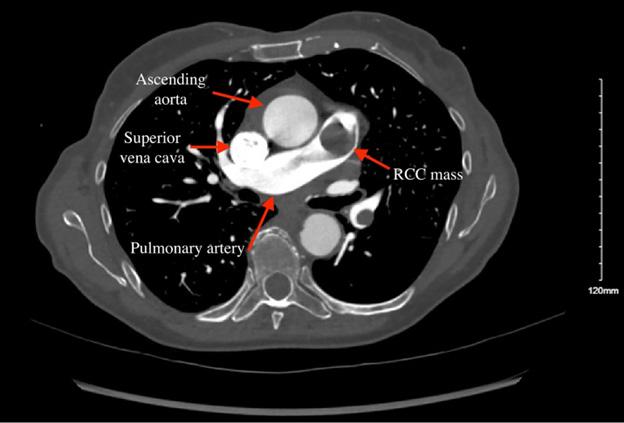

294 Presentation of Renal Cell Carcinoma Invading into the Pulmonary Artery in the Emergency Department: Case Report

S Yang, C Jewell